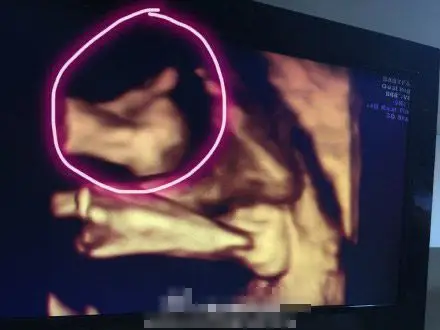

健康胎儿与畸形胎儿同卵双生!|邵逸夫_新浪财经_新浪网

同卵双胞胎,也称为单卵双胞胎,是由同一个受精卵分裂而成的,形成两个